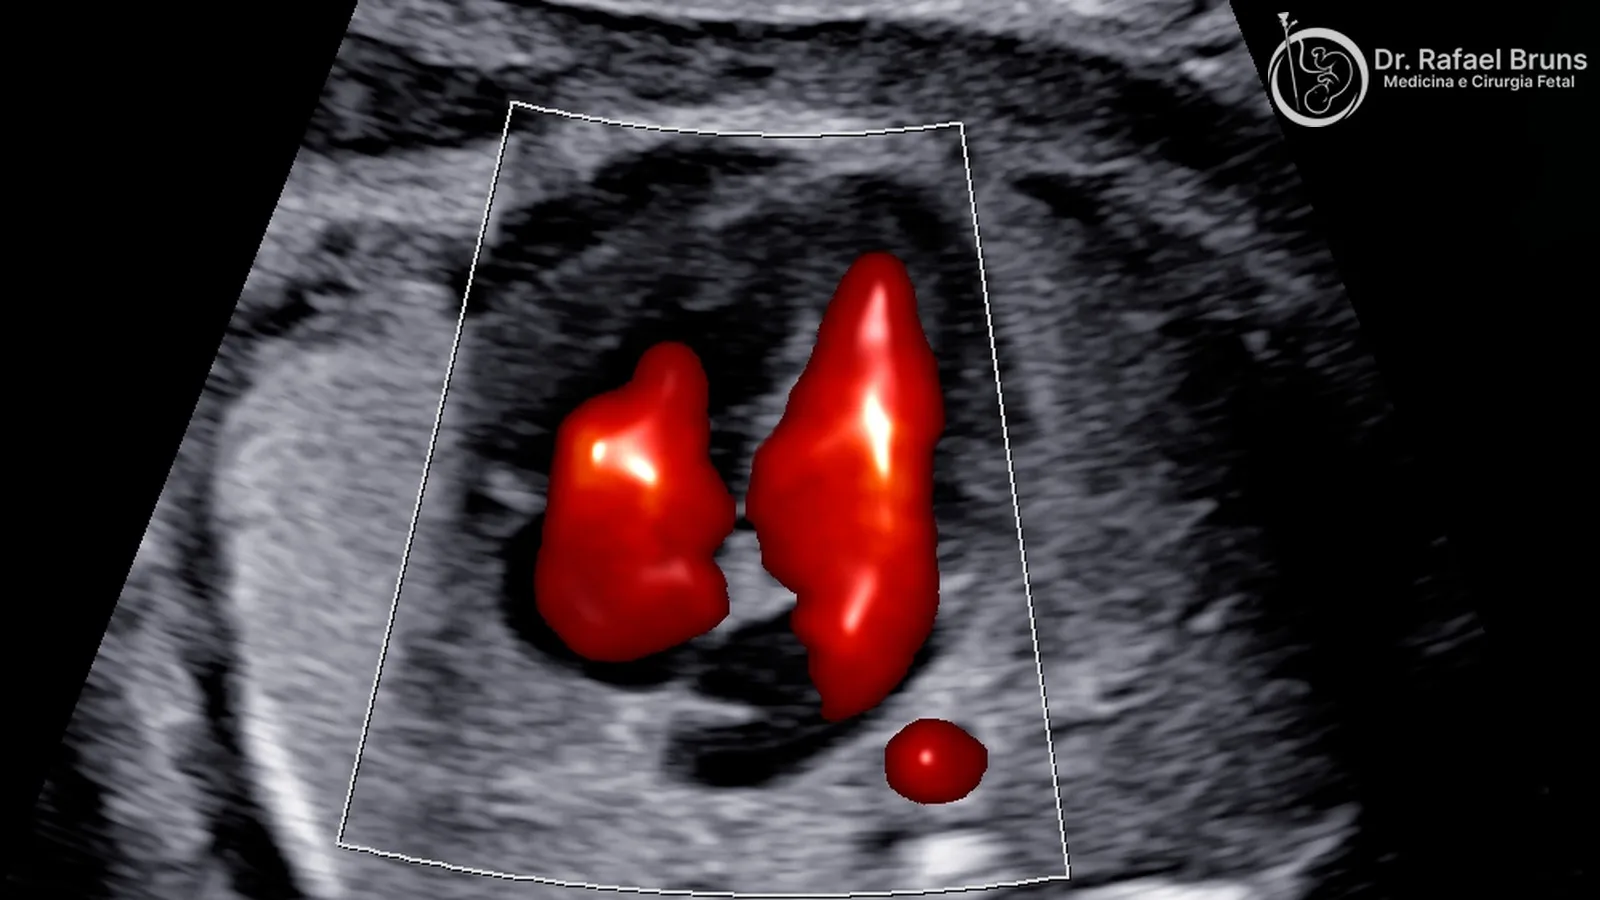

Ecocardiografia fetal em tempo real — avaliação do coração do bebê com mapeamento de fluxo em cores.

A ecocardiografia fetal é um exame diferente em propósito e profundidade. É uma avaliação dedicada exclusivamente ao coração fetal, realizada por profissional com treinamento específico nessa técnica, com protocolo que inclui Doppler colorido em todas as estruturas cardíacas, Doppler pulsátil nas valvas e grandes vasos, avaliação do ritmo e da função ventricular. É o padrão-ouro para o diagnóstico de cardiopatias congênitas antes do nascimento.

Função e fluxo

O Doppler colorido mapeia o fluxo em todas as estruturas principais, identificando regurgitações valvares, estenoses e comunicações anômalas. O Doppler pulsátil nas valvas, grandes artérias, ducto venoso e veias pulmonares avalia velocidades e padrões de fluxo que informam sobre a função cardíaca.